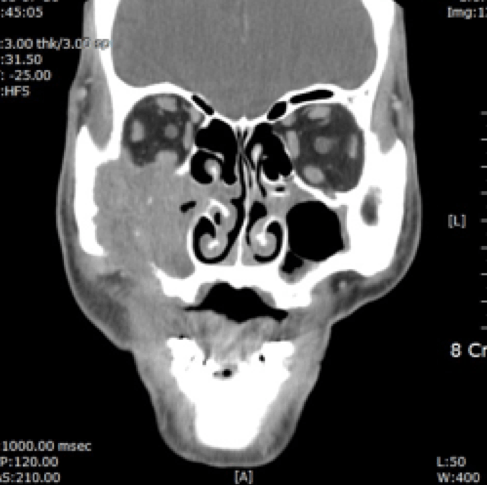

- 전산화 단층촬영 (CT 촬영)

전산화단층촬영 |